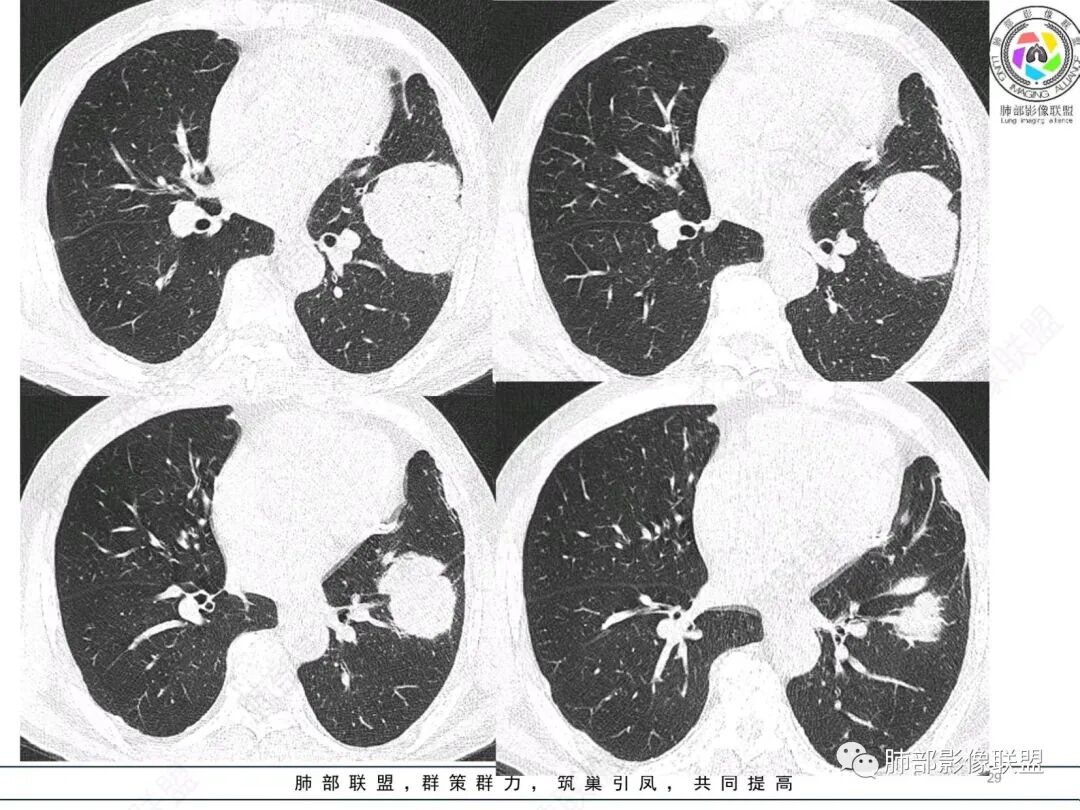

左肺上叶大肿块,膨胀性生长,边界清,密度较低,见部分坏死区,强化弱,肿块见支气管充气V扩张征,分布僵直,枯树枝特点,另一个重要特点血管造影征,淋巴瘤,肿块长轴与胸膜平行,与隐球菌鉴别,隐球荚膜抗原检查,明确诊断经皮肺穿刺。另胸膜钙化(问诊既往有无患胸膜炎病史)。

老年男性,糖尿病病史,消瘦、乏力三个月,影像表现左肺上叶胸膜下团块,有一定张力,内部疏松,可见支气管影及坏死区,增强病灶边缘环形强化,内部未见强化,考虑炎性肉芽肿病变,隐球?奴卡?放线菌?鉴别淋巴瘤。

左肺上叶胸膜下肿块,宽基底与胸膜相连,跨叶裂,边缘清晰膨隆,其内支气管充气,部分扩张、僵直,无明显强化,血管造影征,考虑淋巴瘤,鉴别腺癌

左肺上叶胸膜下肿块,膨胀性生长,边界清晰,密度不均部分坏死,未见强化,病灶内支气管迂曲扩张,病灶长轴与胸膜平行,胸膜下脂肪间隙存在,胸膜钙化,考虑放线菌?毛霉?鉴别淋巴瘤

左肺上叶肿块,宽基底与胸膜相连,跨叶裂,边缘清晰膨隆,可见小分叶,其内支气管充气,部分扩张、僵直,呈枯枝征,支气管达边征,增强无明显强化,可见血管造影征,考虑恶性病变,淋巴瘤,鉴别粘液腺癌。

糖尿病史,慢性病程,左肺巨大肿块,跨叶生长,肿块近端可见充气支气管征及悬浮气泡,轻度圴匀强化,病变长轴与胸膜平行,炎性标志物正常,考虑放线菌,其次淋巴瘤

支气管不像淋巴瘤,肺动脉走也不连续。支气管是断断续续的堵塞和扩张,狭窄。不是那种扩张

我再建一下血管。支气管进入,但是近端推移,堵塞

内部支气管扩张

肺动脉推移为主,边缘部分进入

回头看,内部支气管近端其实不连续,伴随肺动脉不存在

这两点就不符合